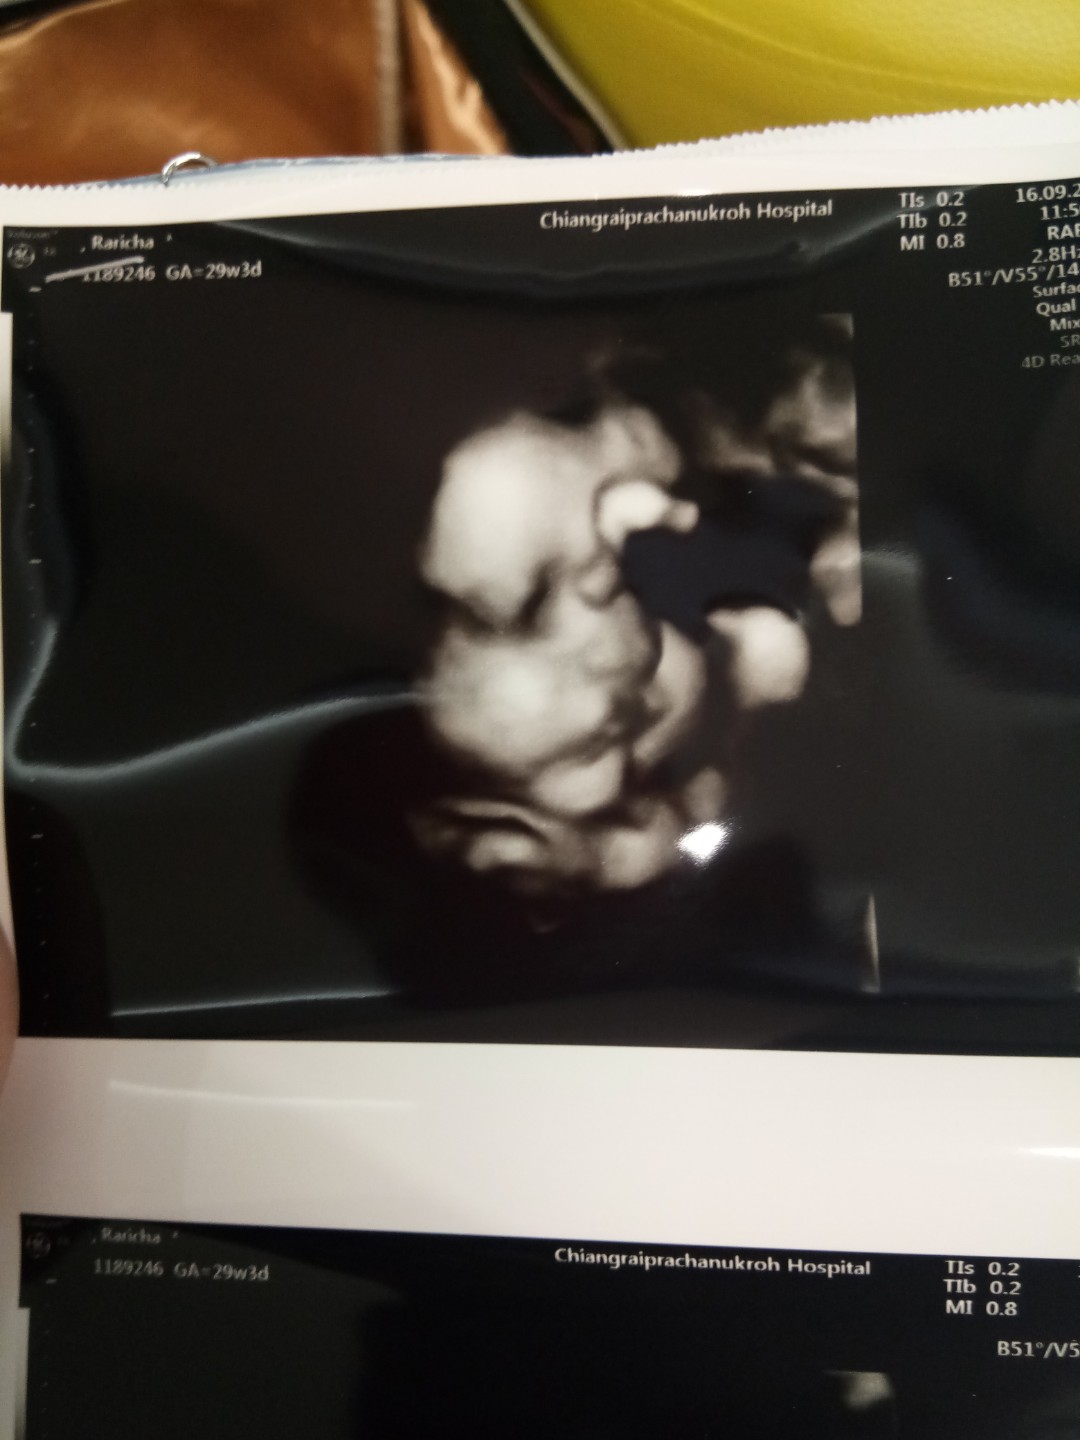

ซาวด์ตอน30+6 ตอนนี้33+4แล้วค่าาา ตอนแม่ซาวด์น้องเบะโชว์ด้วย55555